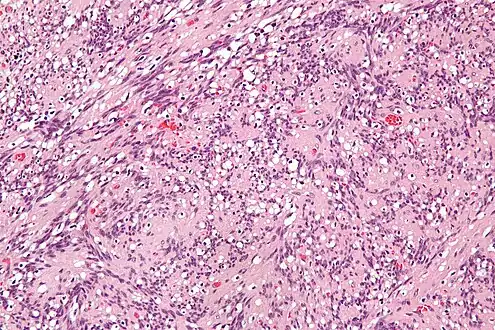

IPMs are diagnosed by examination of the tissue by a pathologist. They have a rim of peripheral lymphoid tissue (remnant of a lymph node) and consist of spindle cells with nuclear palisading. Red blood cell extravasation is common and blood vessels surrounded by collagen with (fine) peripheral spokes (amianthoid fibers) are usually seen.[3]

Immunostains for smooth muscle actin and cyclin D1 are characteristically positive. The main histologic differential diagnosis is schwannoma.

High mag. Intranodal palisaded myofibroblastoma